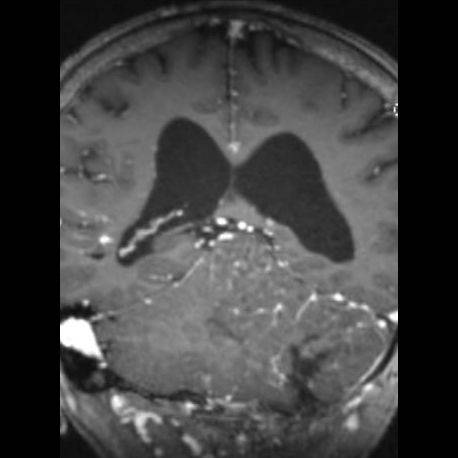

24 yaş, E

Baş ağrısı

Lhermitte duclos

Lhermitte-Duclos hastalığı (Dysplastic cerebellar gangliocytoma)

Dysplastic cerebellar gangliocytoma(Lhermitte-Duclos hastalığı)

Lhermitte-Duclos hastalığı

Displastik serebellar gangliositoma